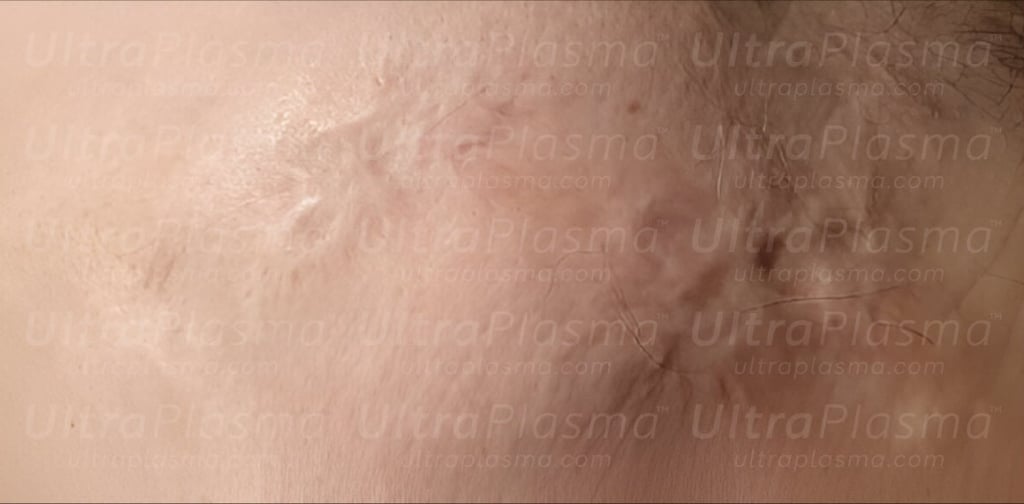

Advanced Scar Treatment Using UltraPlasma™ Multi-Platform Plasma Systems

Scarring, a complex biological response to dermal injury, manifests in various forms including surgical, hypertrophic, keloid, atrophic, stretch marks (striae), and umbilical scars. Traditional treatments often fall short due to the variability in scar biology and patient response. UltraPlasma™, a next-generation dermatological technology integrating arc, argon, and helium plasma modalities, offers a multi-depth, multi-function strategy. This article explores the anatomical, biological, and engineering principles behind scar remediation using UltraPlasma™, including the effects on skin layers, reactive species interactions, and clinical applications.

Scar formation is a natural consequence of dermal injury, often resulting in cosmetic and functional challenges depending on severity, location, and healing dynamics. Modern regenerative dermatology seeks to modulate scar tissue and restore healthy skin architecture through advanced technologies. UltraPlasma™ represents a novel multi-platform plasma treatment that combines arc, argon, and helium plasma modalities for controlled tissue interaction. This article details the mechanisms, anatomical penetration, and physicochemical gas interactions—including ozone (O₃), nitric oxide (NO), and reactive oxygen/nitrogen species (RONS)—targeted at epidermal, dermal, and hypodermal layers. Clinical and histological outcomes in treating atrophic, hypertrophic, and keloid scars on the face and body are discussed.

Scars arise from a disrupted wound healing process characterized by collagen overproduction or tissue loss. Depending on the scar type, tissue architecture, fibroblast activity, and vascularization vary significantly. UltraPlasma™ utilizes tunable plasma emissions to precisely target scarred skin layers and restore healthy tissue dynamics through oxidative, thermal, and biochemical pathways.

5.1 Surgical & Hypertrophic Scars

Arc + Argon combo to reduce raised tissues and normalize pigment.

NO and O₃-mediated ECM restructuring and angiogenesis.

Layered AP-ArP-HeP therapy to address skin tethering and ECM defects.

Vascular and dermal reorganization promoted via RONS signaling.

UltraPlasma™ technology offers a differentiated therapeutic approach through customizable depth and plasma composition. Unlike ablative lasers or monotherapy devices, its triple-mode design allows precise control of oxidative stress, cellular modulation, and structural remodeling. Combined RONS dynamics yield comprehensive antifibrotic, vasoregulatory, and regenerative benefits.

The UltraPlasma™ multi-platform system represents a paradigm shift in scar management. By leveraging the unique interactions of arc, argon, and helium plasma with skin biology and gas chemistry, it enables personalized, multi-layered treatments for a wide range of scar pathologies.